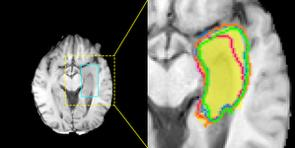

Accurate magnetic resonance imaging (MRI) segmentation is crucial for clinical decision-making, but remains labor-intensive when performed manually. Convolutional neural network (CNN)-based methods can be accurate and efficient, but often generalize poorly to MRI's variable contrast, intensity inhomogeneity, and protocols. Although the transformer-based Segment Anything Model (SAM) has demonstrated remarkable generalizability in natural images, existing adaptations often treat MRI as another imaging modality, overlooking these modality-specific challenges. We present SAMRI, an MRI-specialized SAM trained and validated on 1.1 million labeled MR slices spanning whole-body organs and pathologies. We demonstrate that SAM can be effectively adapted to MRI by simply fine-tuning its mask decoder using a two-stage strategy, reducing training time by 94% and trainable parameters by 96% versus full-model retraining. Across diverse MRI segmentation tasks, SAMRI achieves a mean Dice of 0.87, delivering state-of-the-art accuracy across anatomical regions and robust generalization on unseen structures, particularly small and clinically important structures.